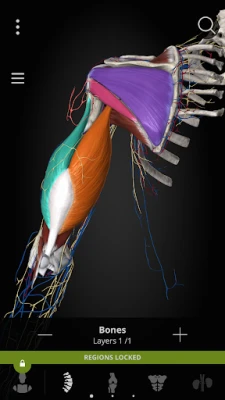

Color-coded organs allow users to view high-resolution anatomical structures supplemented by informative descriptions from a comprehensive textbook ‘Memorix Anatomy’. These are arranged into a proper anatomical hierarchy, meaning learning is structured and easy to understand.

Choose from different themes for a better visual experience, including classic atlas, dark atlas, dark space and cartoon style.

COLORIZE

Set your own color for organs, structures or systems for more effective memorizing.

- User-friendly interface: Zoom, rotate, scale, colorize, isolate, select, hide, and fade all anatomical structures

Color-coded organs allow users to view high-resolution anatomical structures supplemented by informative descriptions from a comprehensive textbook ‘Memorix Anatomy’. These are arranged into a proper anatomical hierarchy, meaning learning is structured and easy to understand.

Choose from different themes for a better visual experience, including classic atlas, dark atlas, dark space and cartoon style.

COLORIZE

Set your own color for organs, structures or systems for more effective memorizing.